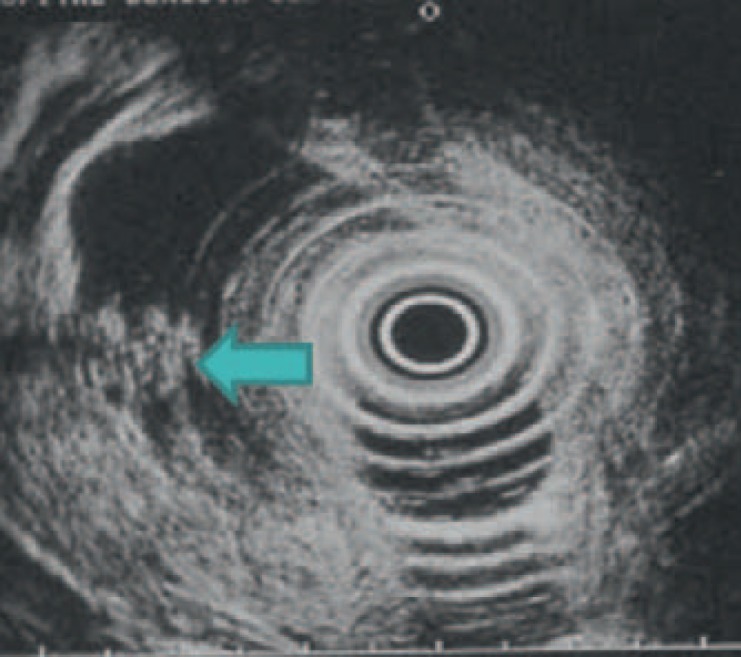

Fig. 10.

Endoscopic ultrasonography of the same patient showing a small area in which microcysts are visible (layered aspect) (arrow) (image courtesy of Dr. Marie Pierre Vullierme, Hôpital Beaujon).